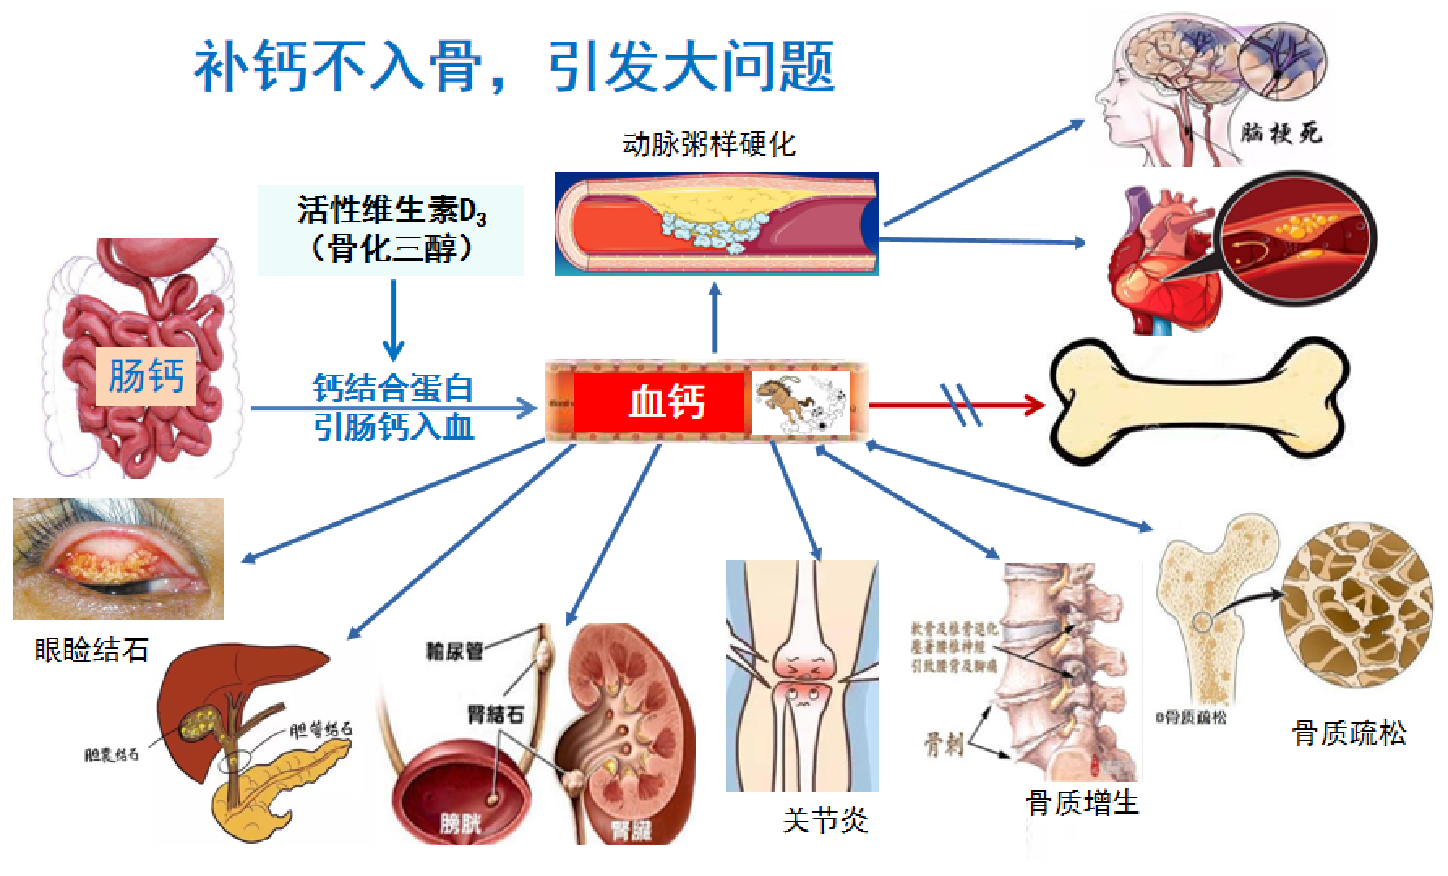

钙离子吸收入血以后,就像一匹匹脱缰的野马,随着血液循环四处奔腾。最喜欢去有炎症的部位凑热闹。身体哪个部位有炎症,钙就去哪里沉积。所以,补钙很重要,补钙有风险,补钙不入骨,会惹大麻烦。

七.离子钙带来的烦恼和疾病

除了动脉粥样硬化外,钙钙参与诸多疾病的发生和发展。如胆肾结石,眼睑结膜结石,关节炎,骨质增生。补钙补入骨,骨质得不到补充,自然还会继续骨质疏松。

钙参与多种疾病的发生和发展

有什么好办法既能让钙保护骨骼,正常行使它的生理职责,而又不让它乱跑乱窜伤害身体呢?到底应该如何补钙,才能既防治骨质疏松症,又不会给身体造成危害呢?